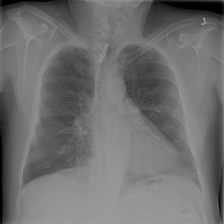

To pre-train a high-performance X-ray foundation model, the first thing we need to do is the collection of large-scale X-ray images. Therefore, a large-scale and high-resolution dataset that contains X-ray medical images is collected for the pre-training. Some representative samples are visualized in Fig. 3.

As shown in Fig. 8, we provide some representative samples predicted by our model. The and column are the raw X-ray images, the and column are masked images, and the and column are the reconstructed images. We can find that our proposed context-aware masking strategy guided MAE framework predict the masked tokens well.

As shown in Fig. 9, given the text lungs, we can find that the activation maps can accurately highlight the target regions. Therefore, we can achieve a higher performance on the downstream tasks. However, the activation maps are imperfect, as the background regions are also highlighted.

4.7.4 Disease Prediction

As shown in Fig. 11, given the X-ray image from the RSNA-Pneumonia dataset and all the labels (binary classification) we need to recognize, our model can predict the disease accurately.